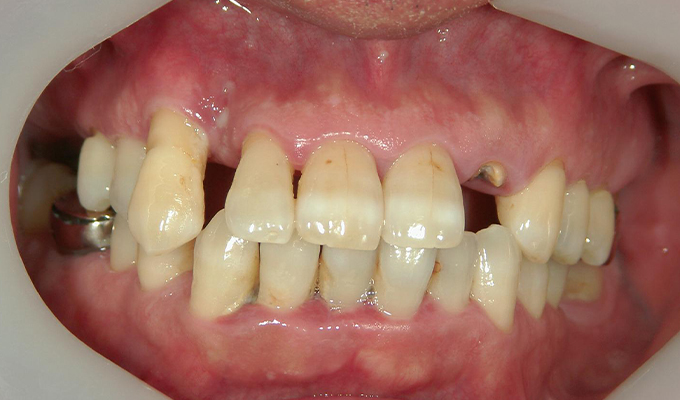

case1インプラントとメタルボンドブリッジの症例

初診時(2010年)

- 初診時の年齢

- 60代女性(2010年)

- 主訴

- ちゃんと咬めるようになりたい。最近孫が生まれたから一緒に歌ったりしたいけど、今は歌うこともできないから・・・・。と

- 治療内容

- 5年ほど前に入れ歯を作ったそうですが合わなかったので使用してなかったせいか前歯がグラグラになっていて今にも抜けそうな状態でした。

保存が難しい歯を抜歯し、上はインプラント8本、下は奥歯にインプラント4本埋入しました。

補綴は変色しないメタルボンドを選択されたので治療完了して11年経過してもとてもきれいな状態で維持されています。

初診時にお話しされていたお孫さんも中学2年生になったそうで、歯の治療をしたおかげで充実した毎日が送れてます、とメンテナンス時もいつも嬉しそうにされています。